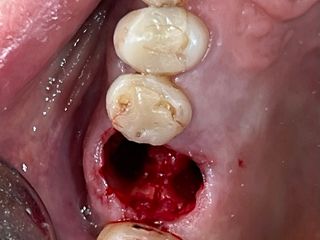

5. Occlusal view after atraumatic tooth extraction.

5

6. Immediate implant placement Ø 6.4mm Axiom® X3, 4 mm deep from the gum margin in the bone furcation for mucointegration.

6